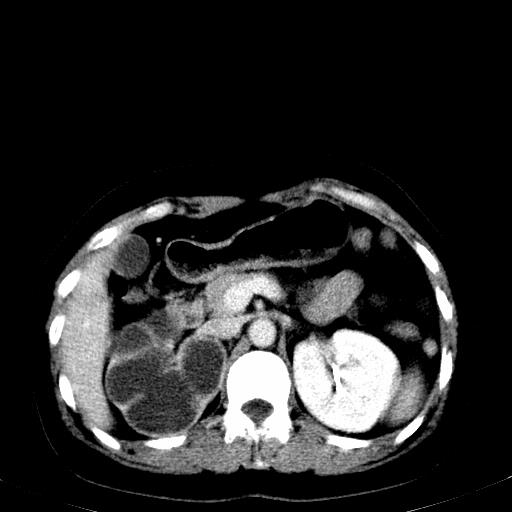

右肾重度积水,以肾盏积水明显,有分隔,上段输尿管轻度扩张,管壁增厚,考虑肾结核可能,请结合尿检查,胸部拍片排除肺结核。

右侧肾积水、左侧肾结石

右侧肾积水、左侧肾结石  ,要排除右肾结核可能。

右肾重度积水,建议ct向下扫描或逆行造影,左肾及左输尿管结石 .

右侧肾积水、左侧肾结石 ,原因待查

1)不排除右肾结核可能。2)左肾及左输尿管上段结石?

要排除右肾结核可能

右肾积水、左侧肾脏结石,建议进一步检查原因除外左肾结核可能